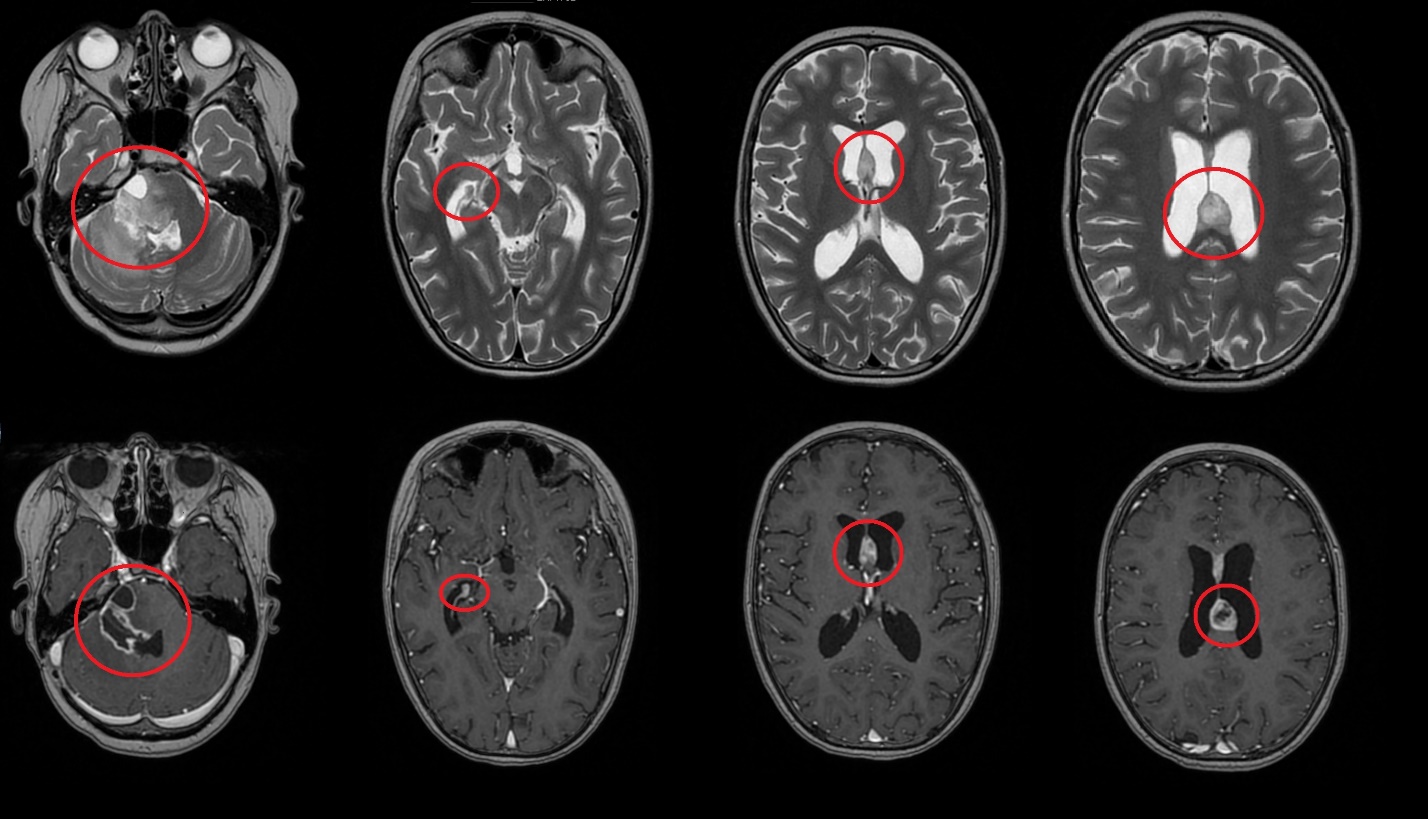

Результаты. У 19 пациентов (50 % от 38 прошедших биопсию) по данным иммуногистохимического анализа послеоперационного материала была выявлена мутация К27М в гене H3F3A. У 6 (15 %) пациентов из 38 МРТ в сроки от 2 до 5 мес (медиана – 4,5 мес) после окончания лучевой терапии выявлено нехарактерное прогрессирование ДСГ в виде метастазирования по желудочковой системе головного мозга. У остальных пациентов когорты исследования, не проходивших процедуру биопсии, подобный характер прогрессирования не наблюдался (p<0,002): у них, как правило, отмечался продолженный рост опухоли (n=96), у 4 больных диагностировано лептоменингеальное метастазирование по спинному мозгу.

Заключение. Нами выявлены случаи нетипичного прогрессирования ДСГ в виде метастазирования по желудочковой системе у детей после открытой биопсии опухоли. Есть основания полагать, что биопсия могла способствовать диссеминации ДСГ по ликворным пространствам. Необходим поиск альтернативных методов оценки молекулярно-генетических характеристик ДСГ.